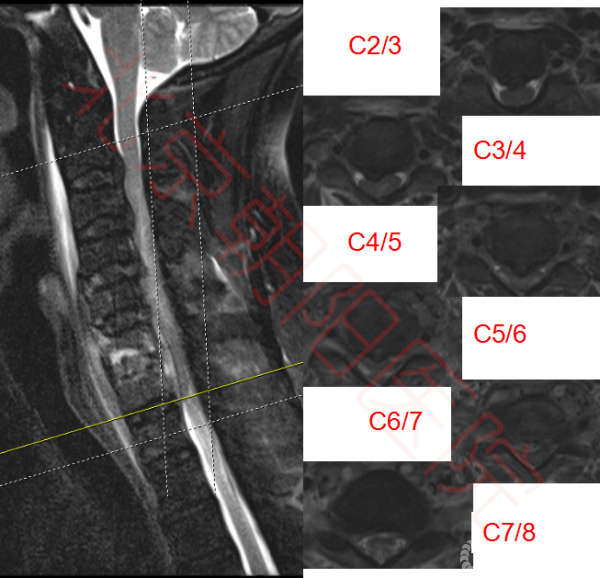

颈椎核磁如图:可见多节段脊髓压迫。

图2:如图可见脊髓多节段受压,C6、C7椎体及椎间盘高信号,C6-C7椎体后方可见高密度影,C5-C8椎体前方高密度影。脊髓内可见高信号区域